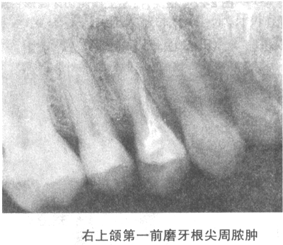

20、根尖周病牙片

【答案】根尖周炎

1.急性根尖周炎

急性期早期X线上无骨质破坏,根尖区牙周膜间隙略有增宽。脓肿形成后,患牙根尖部有不规则骨质破坏区,边界不整齐,但范围局限。

2.慢性根尖周炎

依病变的性质不同,分为三种(图4-2)。

(1)慢性根尖脓肿 X线表现为患牙根尖区有一边界清楚但不十分整齐锐利的低密度透射区,形状规则或不规则,密度不均匀,根尖区骨硬板消失。

(2)根尖肉芽肿 X线表现为位于患牙根尖区形态规则,呈圆形或椭圆形的骨质破坏区,直径多不超过1cm,周界清晰,但无致密的骨白线。

(3)根尖囊肿 X线表现为位于患牙根尖的形状规则、边缘清晰锐利的低密度透射区,呈圆或椭圆形。病源牙的根尖位于囊腔中,牙周膜间隙及硬骨板消失,囊肿边缘有一薄层致密的骨白线。